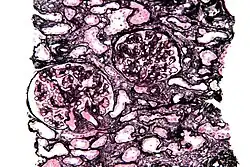

Jones' stain, also Jones stain, is a methenamine silver–periodic acid–Schiff stain used in pathology.[1] It is also referred to as methenamine PAS which is commonly abbreviated MPAS.

It stains for basement membrane and is widely used in the investigation of medical kidney diseases.

The Jones stain demonstrates the spiked GBM, caused by subepithelial deposits, seen in membranous nephropathy.